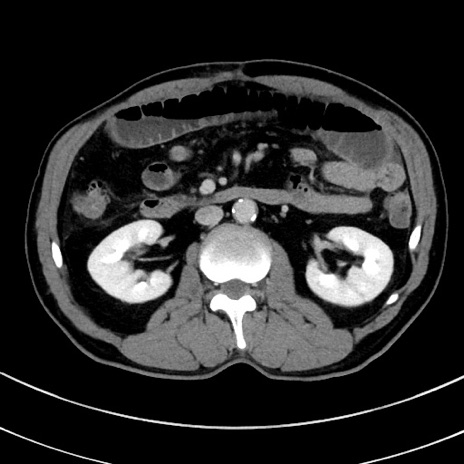

症例8(横断像)

【症例】 60歳代男性

【主訴】 黒色吐物

【現病歴】 4日前から嘔気自覚、2日前の朝食後にも嘔気あり、自分で手で嘔吐反射起こし嘔吐したところ血が混ざっていたため受診。

【既往歴】 5年前汎発性腹膜炎を伴う急性虫垂炎で手術、高血圧、前立腺肥大症、高脂血症

【身体所見】 腹部正中に手術癩痕あり 腹部平坦・軟圧痛なし膨満感あり

【データ】WBC 8400、CRP 4.54